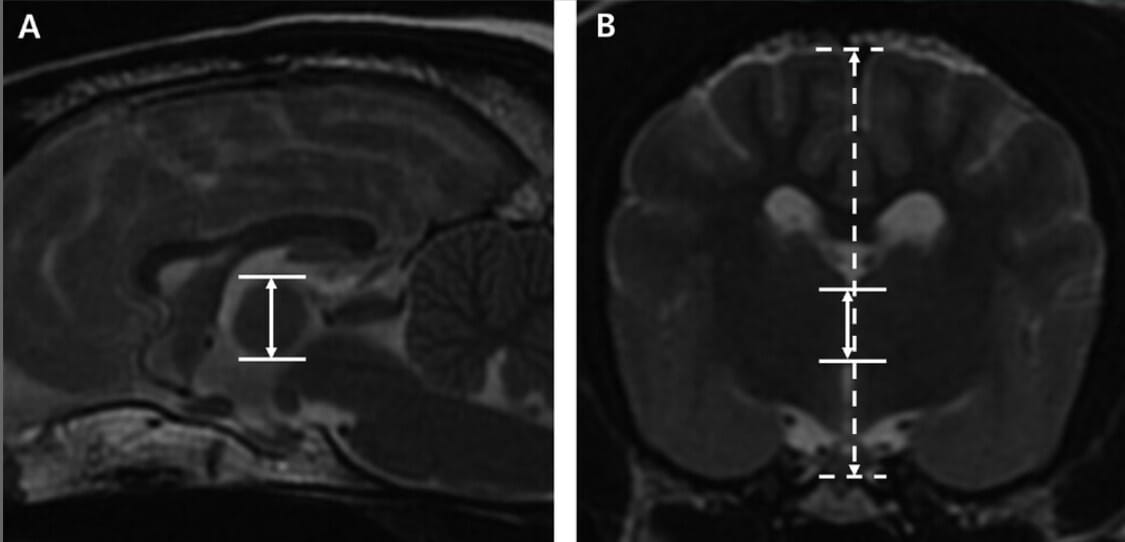

Magnetic resonance imaging (MRI) T2-weighted sequence images of a dog in the sagittal (A) and transverse (B) planes. (A) ITAt was measured vertically from the dorsal-to-ventral aspect of the interthalamic adhesion at the thickest level. The solid white lines and solid double-headed arrows indicate the ITAt and the measurement of ITAt, respectively. (B) The ITAt was measured vertically from the dorsal-to-ventral aspect of the interthalamic adhesion at the level where it was apparently the thickest. The cerebral height was measured perpendicularly from the dorsal aspect of the cerebrum to the base of the skull at the same level. The solid white and dashed lines indicate the ITAt and the height of the cerebral parenchyma, respectively. Solid and dashed double-headed arrows indicate the measurement of ITAt and the height of the cerebral parenchyma, respectively. ITAt: interthalamic adhesion thickness, ITAr: ITA-to-cerebral height ratio.